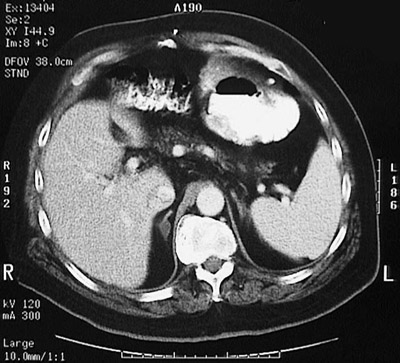

Click on the adrenal adenoma in the CT scan above:

This abdominal CT scan with contrast demonstrates an incidental right adrenal cortical adenoma that is about 1 cm in size. If the patient is asymptomatic with no demonstratable abnormal laboratory findings, then such a lesion is best left alone.